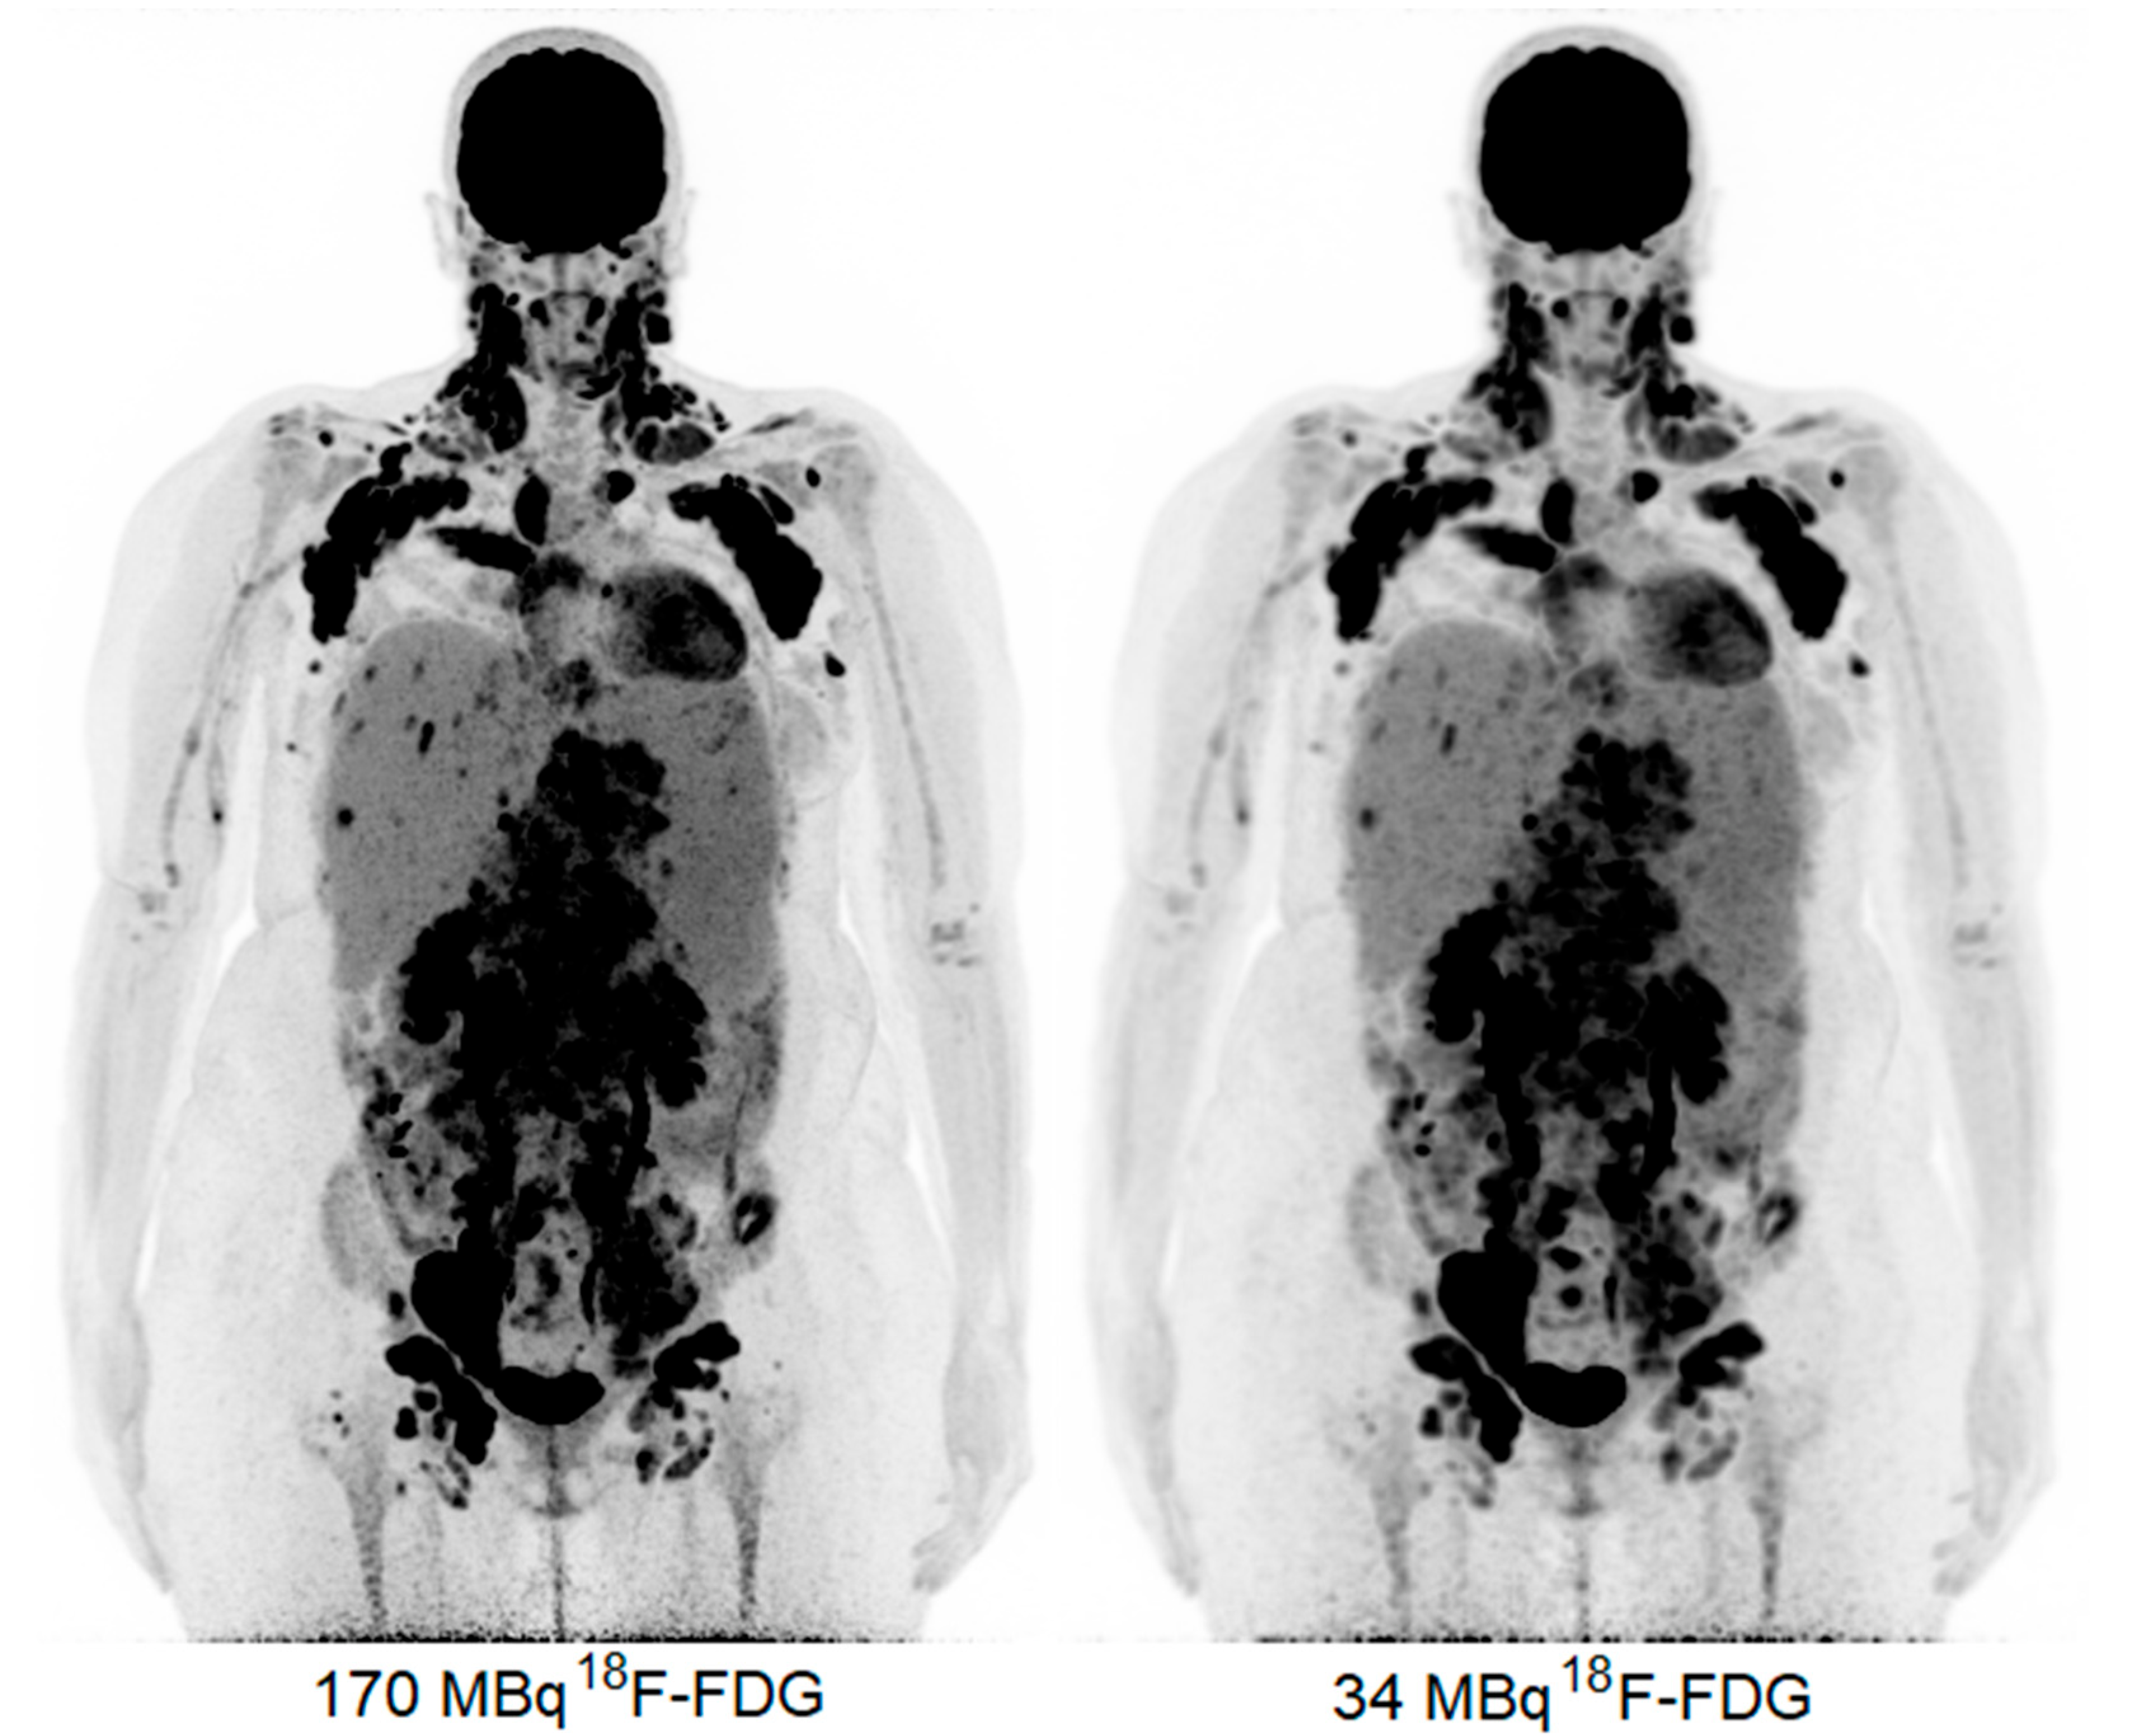

2. Case Presentation